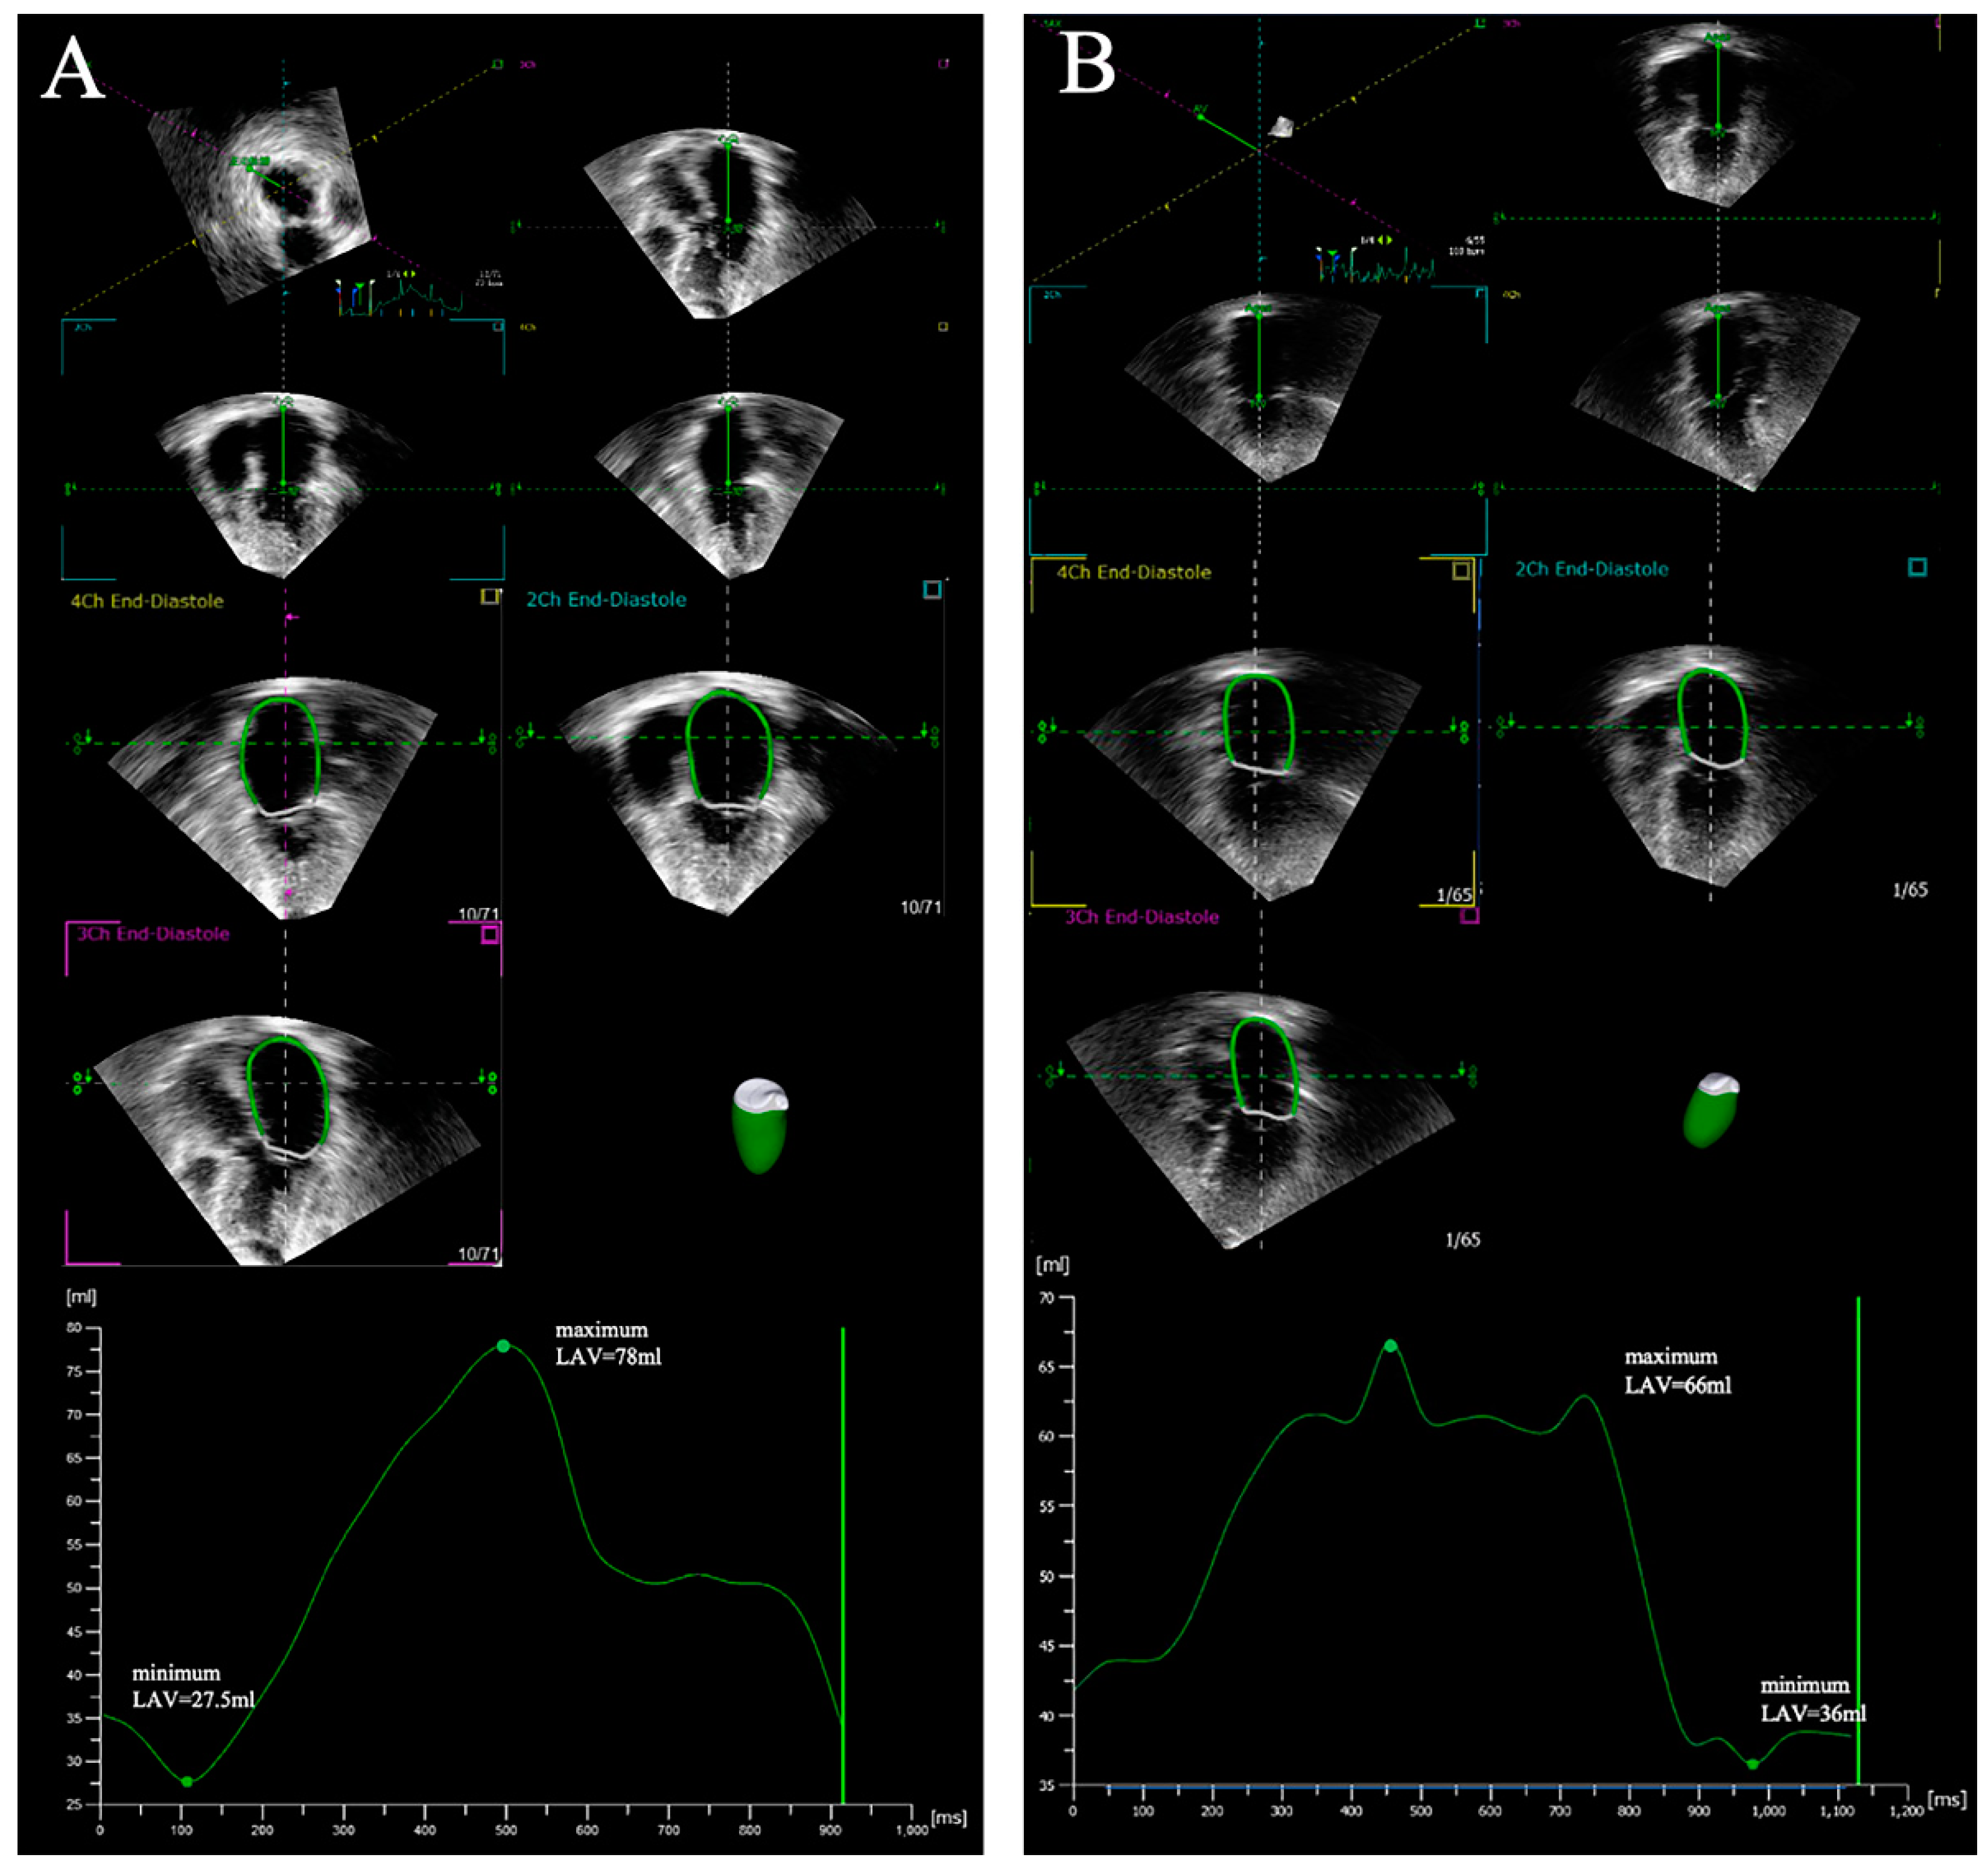

3.1. Real-Time Three-Dimensional Echocardiography

| LAV | Left atrium volume | Maximum LAV and minimum LAV are measured using the modified Simpson biplane method at the end-systolic frame preceding mitral valve opening and the end-diastolic frame preceding mitral valve closure, respectively |

| LAVi | Left atrium volume index | Maximum LAVi and minimum LAVi are measured using the modified Simpson biplane method at the end-systolic frame preceding mitral valve opening and the end-diastolic frame preceding mitral valve closure, respectively, and indexed to body surface area |

| LAEi | Left atrium expansion index | (Maximum LAV–Minimum LAV)/Minimum LAV |

| Total LAEF | Total left atrium emptying fraction | (Maximum LAV–Minimum LAV)/Maximum LAV |